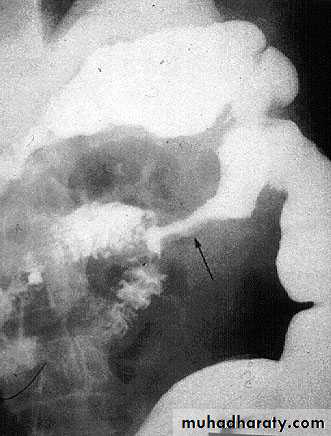

Acute inflammation progress in to chronic inflammation when there is persistent infection, when there is foreign body, etc.-Ulcer

is defined as loss of continuity in an epithelial surface. or excavation of the surface of an organ or tissue produced by the sloughing of inflammatory necrotic tissue.Acute inflammation

UlcersFistulas

Chronic ulcer.Chronic abscess cavity.